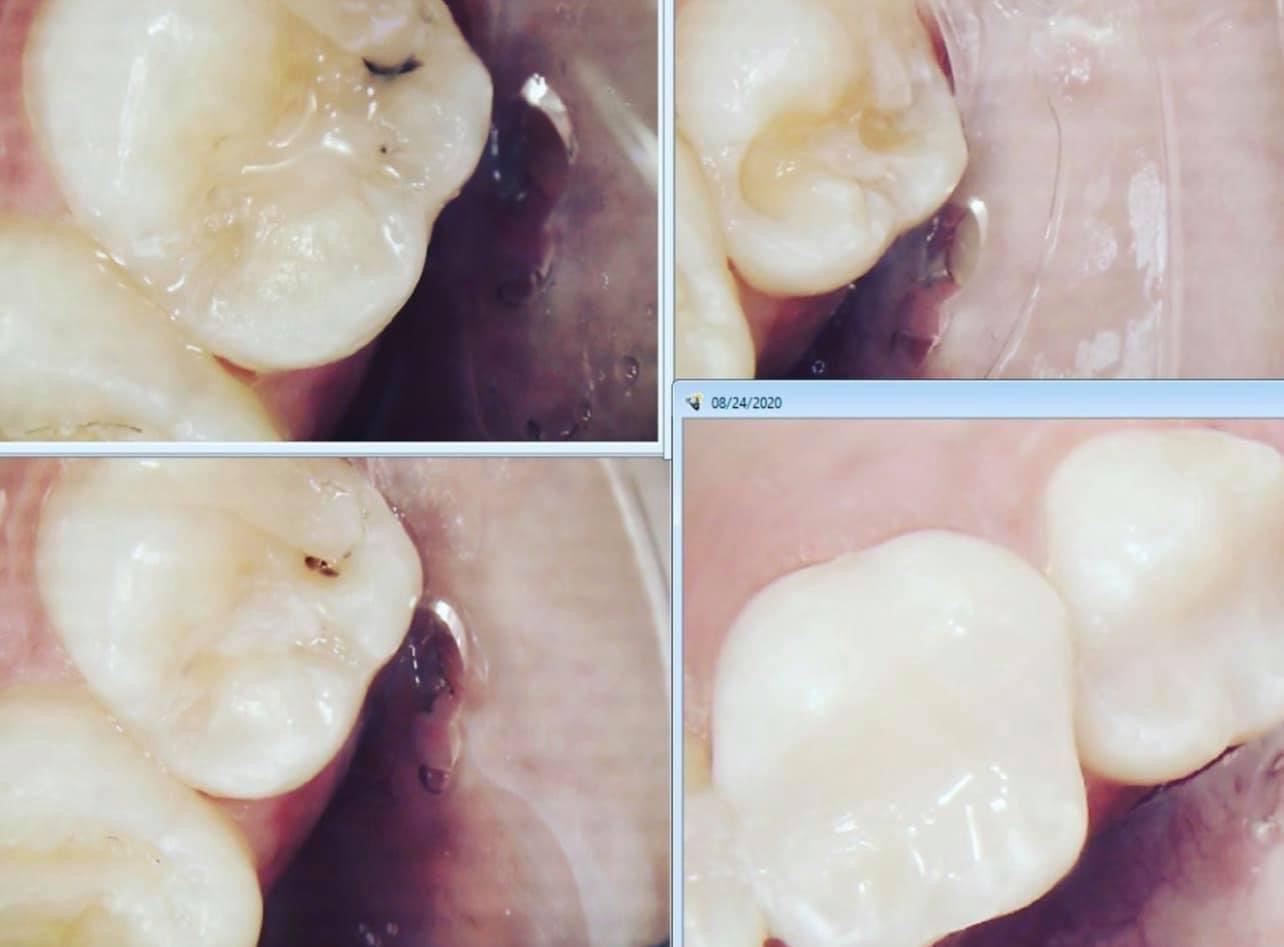

By using advanced techniques to detect cavities early, we help patients protect their teeth before problems become painful or expensive.

With thousands of hours of extra CE courses since completing school Doctor TingTing has taken dentistry to the next level with advanced clinical techniques and diagnosis tools most dentists have never even heard of.

Techniques you won't experience at your average dentist